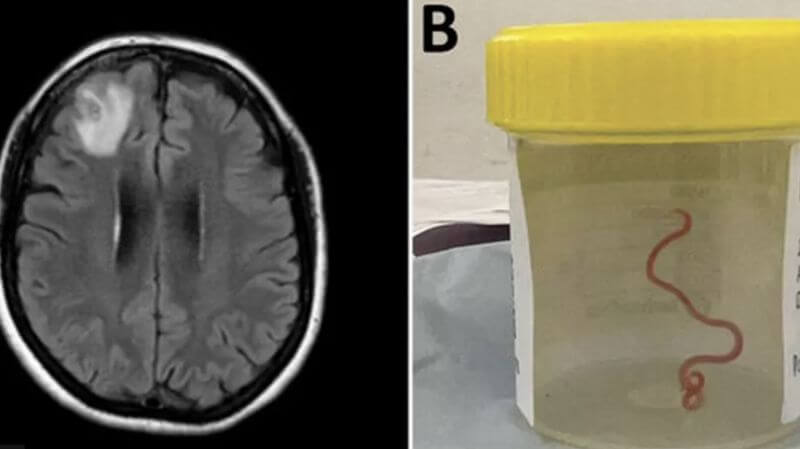

Tibbdə ilk: Avstraliyada qadının beynindən canlı qurd çıxarıldı

Avstraliyada bir qadının beynindən 8 sm uzunluğunda yuvarlaq qurd çıxarılıb. İndex.az xəbər verir ki, hadisə ötən il Kanberrada cərrahiyyə əməliyyatı...